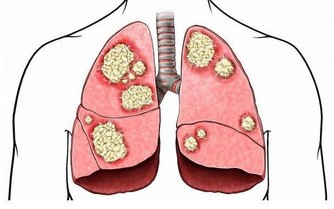

這些宿便堆積在腸道內發酵、腐敗,並不斷產生各種毒素、毒氣,被腸粘膜吸收到血液並輸送到身體各個細胞,首先造成腸內環境惡化、腸胃功能紊亂,既而引發內分泌失調、新陳代謝紊亂,最後引發各種病症,促使人體衰老與死亡。 可以毫不誇張地說,腸道問題是人體萬病之源。 我國古代中醫里有個「陰陽水清腸方」,就是專門用來清除宿便,防止結腸功能失調,可以讓人「不死」的秘法。李時珍《本草綱目·水·生熟湯》:「以新汲水百沸湯合一盞和勻,故曰生熟。今人謂之陰陽水」。 此句是指:從井裡新提的生水和剛煮開的水各一碗混和均勻便是「陰陽水」。 然現代社會水污染嚴重,誰敢冒著「污染水」中毒的風險去喝生水? 【其具體方法】 一、陰陽水清腸方: